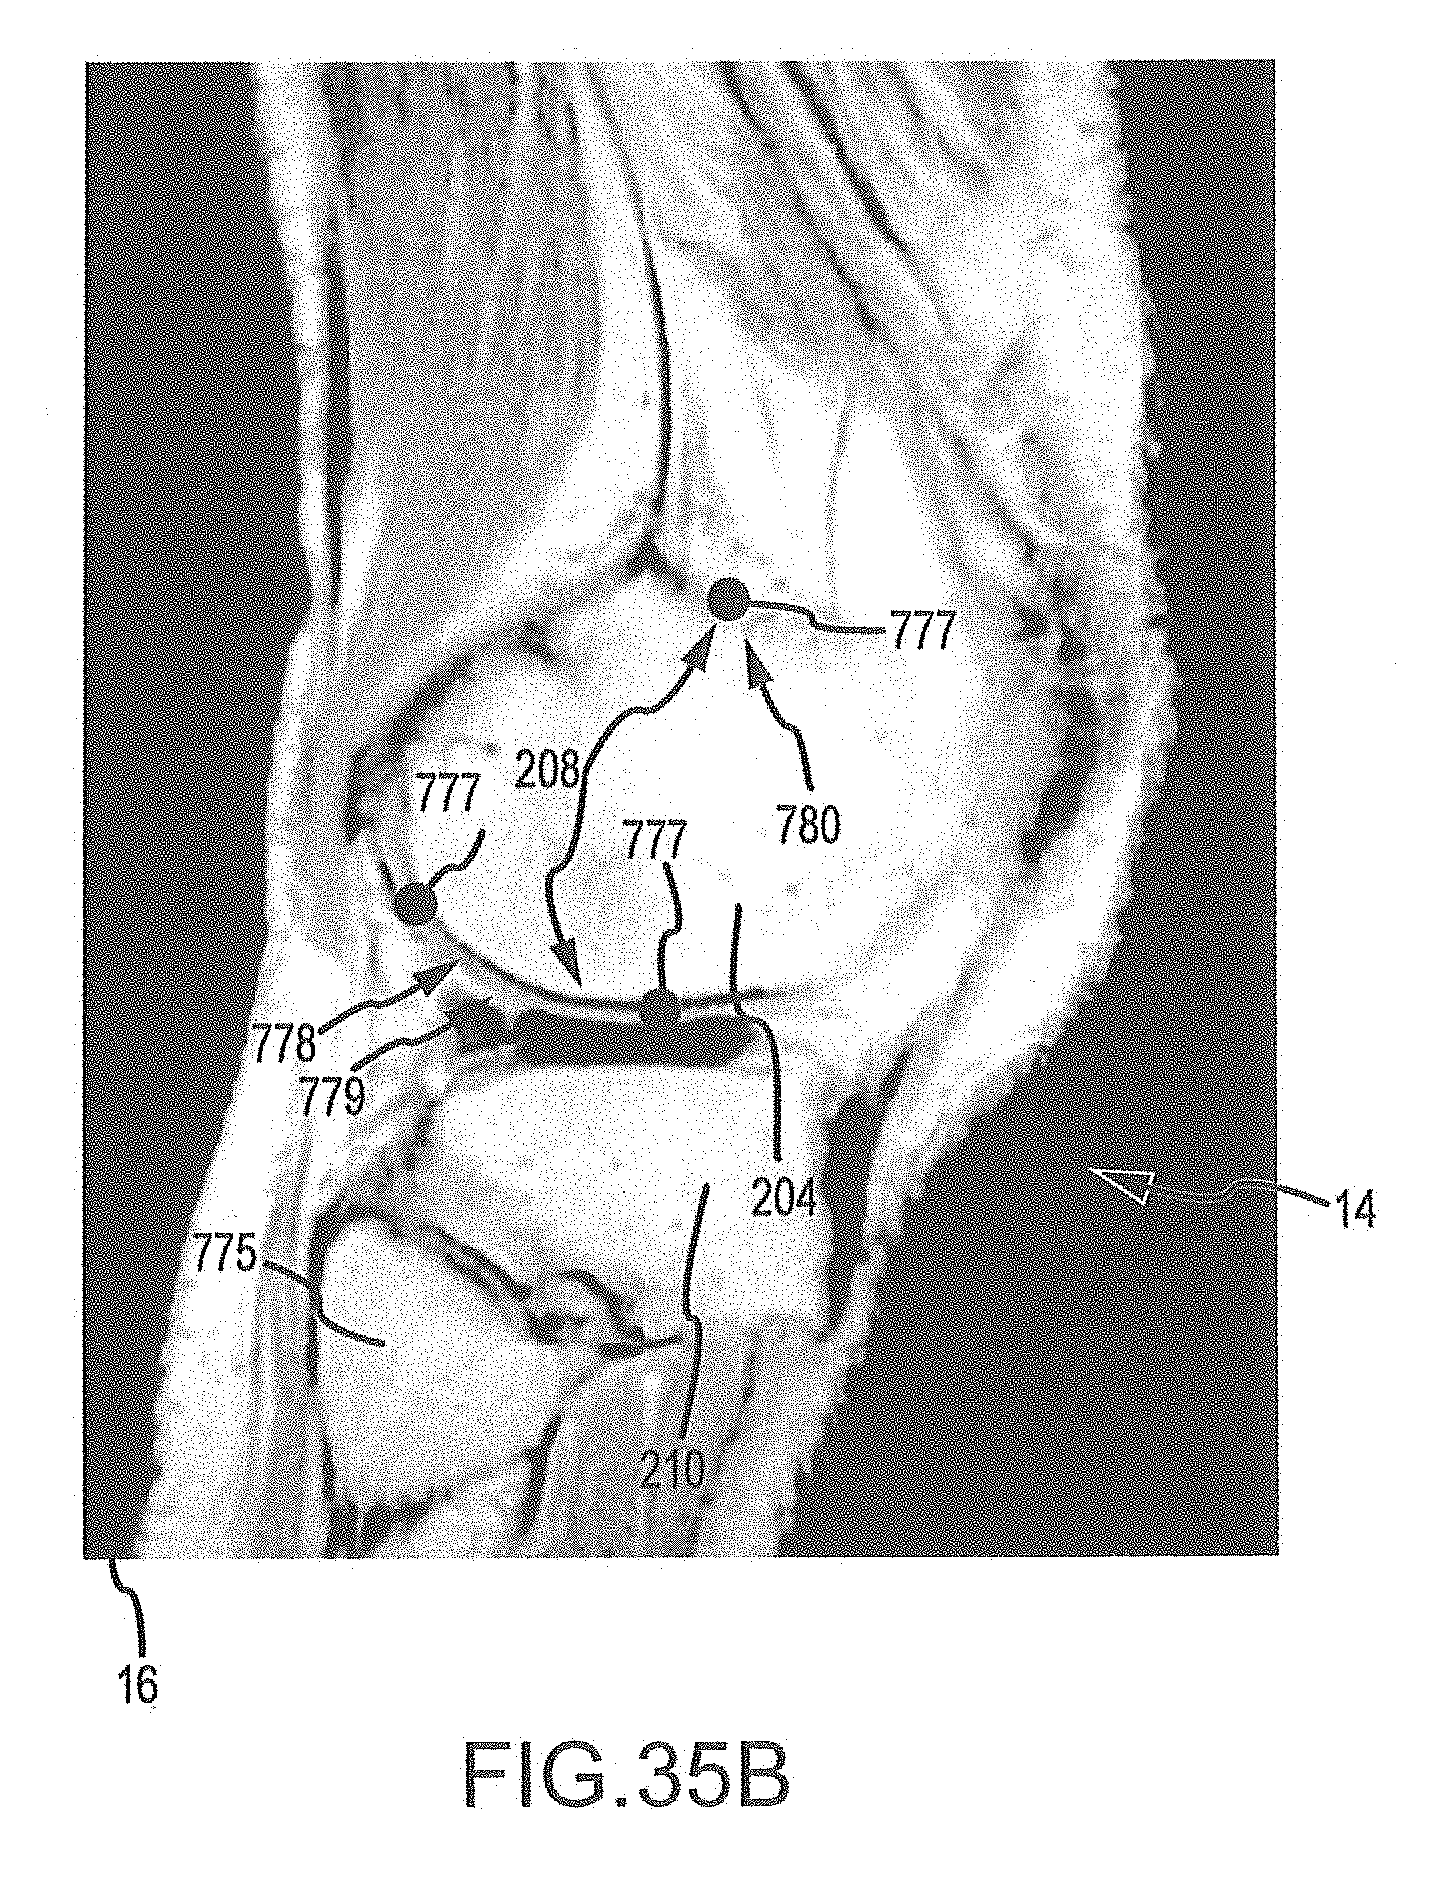

FIGS. 35A-35H are a series of sagittal image slices wherein landmarks have been placed according the process of FIG. 34.

FIG. 38B is an image slice with a contour line representing the approximate segmentation mesh surface found in operation 770c of FIG. 37, the vectors showing the gradient of the signed distance for the contour.